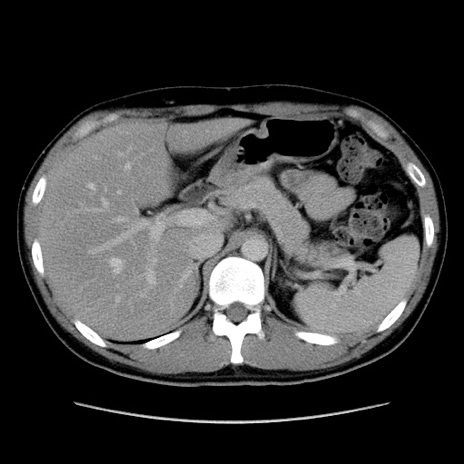

症例36(横断像)

【症例】20歳代 男性

【主訴】心窩部痛

【現病歴】今朝より上腹部痛あり。一旦軽快していたが再度出現したため救急要請。昨日夕に白身の魚を含む刺身を食べた。

【身体所見】BP 136/89mmHg、HR 74/min、BT 37.0℃、腹部:膨満、軟、心窩部に圧痛あり。反跳痛なし、筋性防御なし、腸雑音やや亢進あり。

【データ】WBC 17700、CRP 0.48